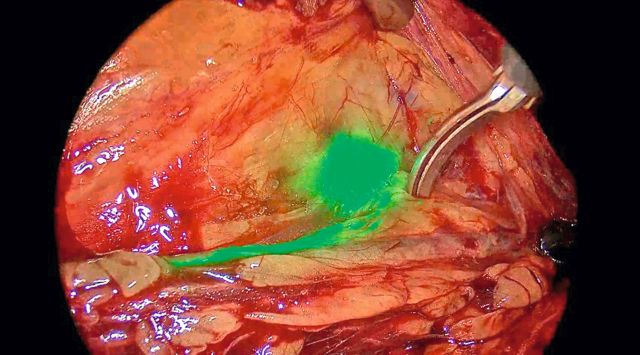

RAISN – Robotisch-assistierte ICG-gesteuerte Sentinel-Lymphknoten-Biopsie bei Hodentumorpatienten